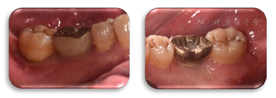

47叩痛(-),不松动,远中及颊侧中央PD7~9 mm,余位点PD3~4 mm,BI2-3,颊侧中央牙龈退缩约2 mm,无附着龈,舌侧牙龈无明显异常(图6,图7)。正中合未及早接触,侧方合未及合干扰,cbct示47颊侧及远中牙槽骨吸收超过根长2/3,颊侧骨缺损深约9 mm,宽约4 mm,远中骨缺损深约10 mm,宽约7 mm(图8,图9)